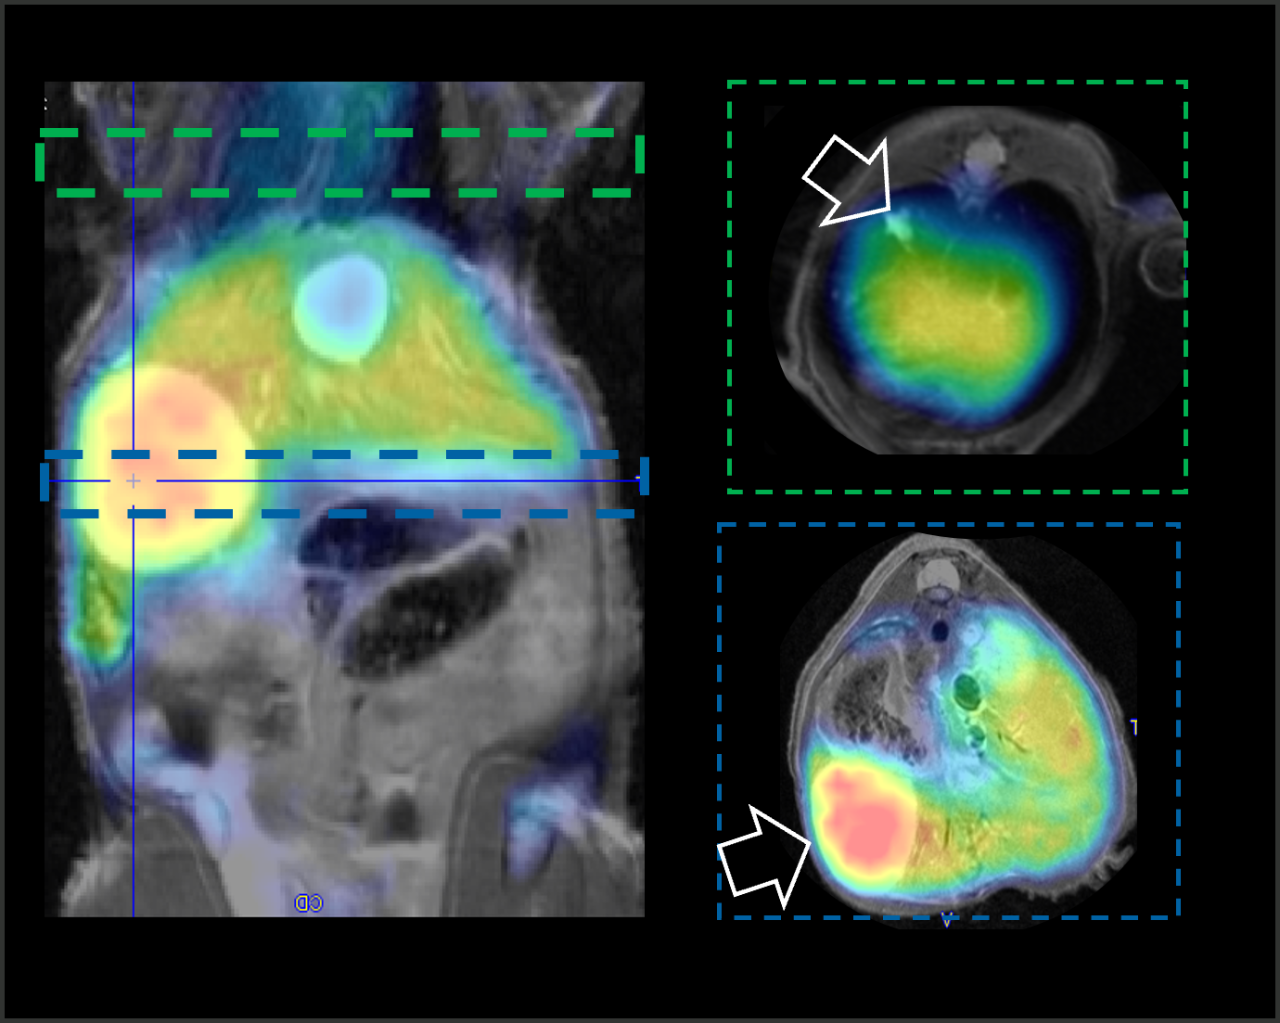

Total body PET/MRI images of mice

Imaged at pre-injection and 1, 5, 30, 45 mins post-injection of 0.1 mmol/kg [52Mn]Mn-2CHyd or [52Mn]Mn-1CHyd.

Courtesy Yingying Ning , Iris Yuwen Zhou, Nicholas J Rotile et al. MGH – USA

Reference: J Am Chem Soc. 2022 Sep 14;144(36):16553-16558.